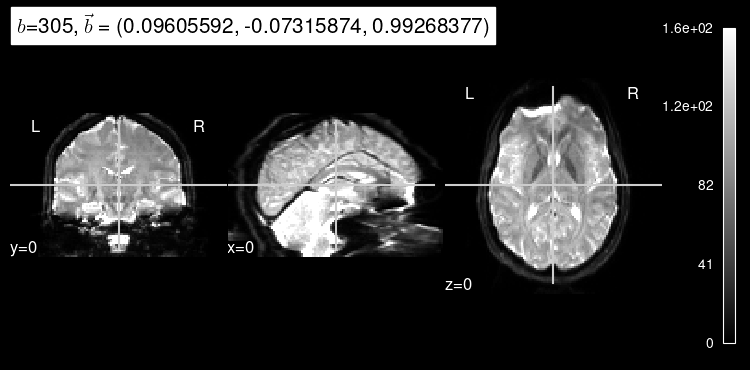

plot_dwi(predicted, dmri_dataset.affine, gradient=data_test[1]);

As expected, the b=0 doesn’t look very much like the particular left-out direction, but it is a start!

plot_dwi(np.squeeze(data_test[0]), dmri_dataset.affine, gradient=data_test[1]);